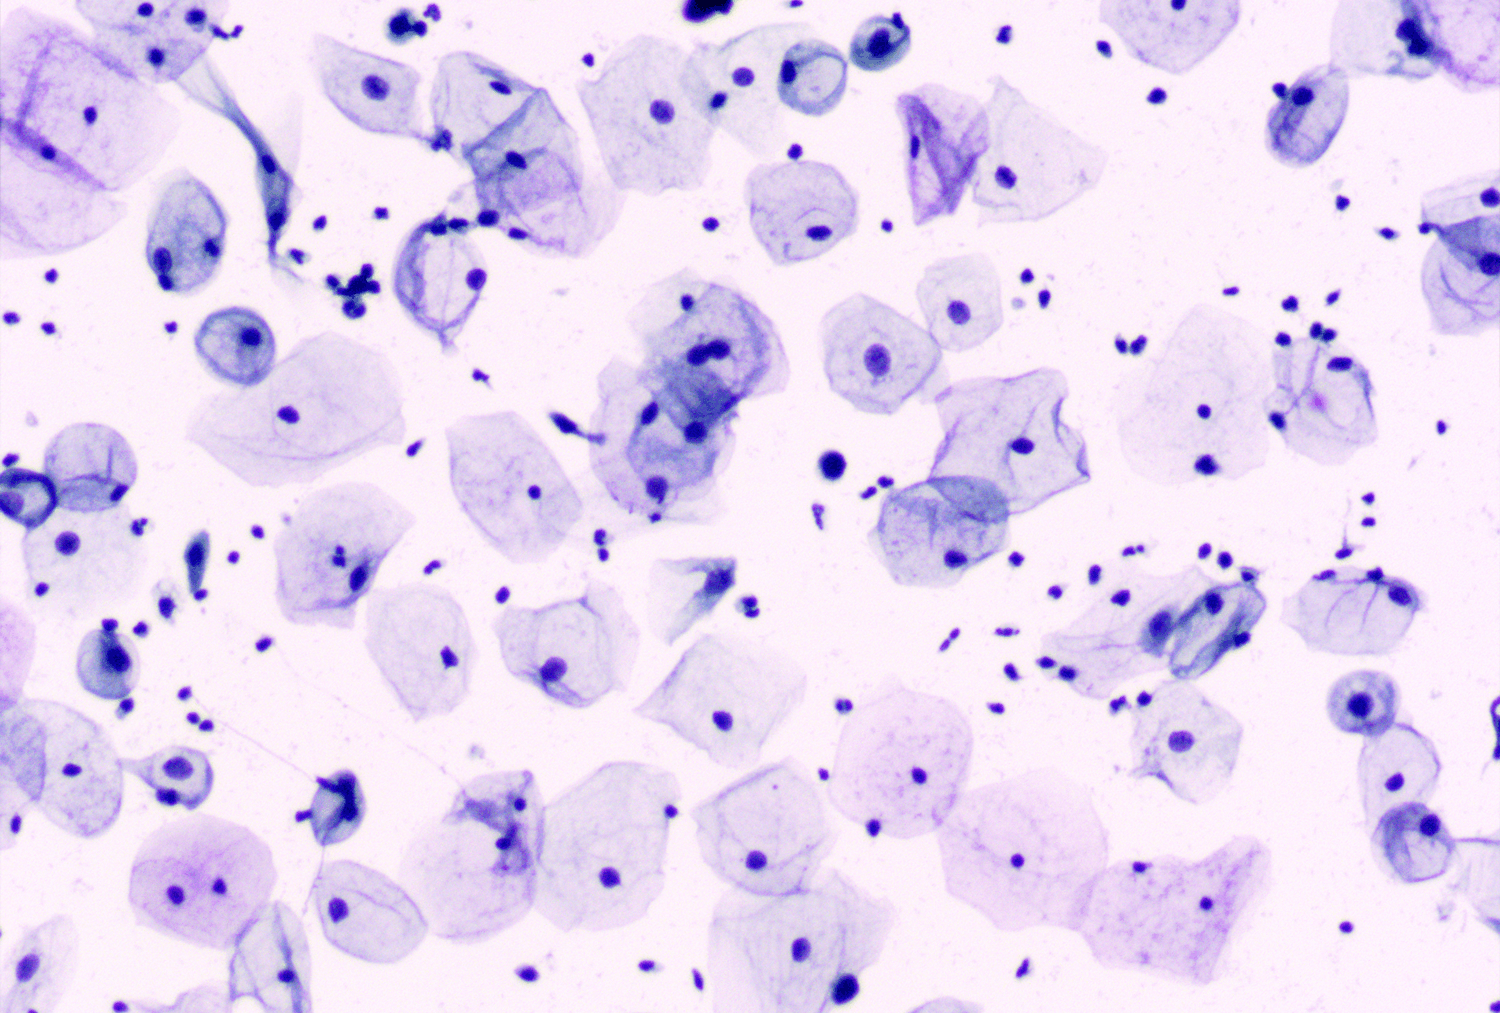

The Cytology department at Padmashree Diagnostics specializes in the evaluation of individual cells to detect early signs of disease. By analysing samples obtained from fine-needle aspirations, body fluids, and exfoliated cells, our team identifies cellular changes that may indicate infections, inflammatory conditions, or precancerous and cancerous lesions. Each specimen is handled with precision to maintain cell integrity and diagnostic clarity.

• Microscopic examination of cheek cell smear to detect infections, inflammatory changes, premalignant lesions, and cytological abnormalities accurately.

• Analyzes exfoliated buccal mucosal cells to identify cellular abnormalities, infections, dysplasia, and early malignant changes effectively.

• Traditional Pap smear screens cervical cells to detect precancerous changes, infections, and early cervical cancer effectively.

• Liquid-based cytology Pap smear improves sample quality for detecting cervical abnormalities, infections, and precancerous lesions accurately.

16 Smear For Cytology

• Microscopic evaluation of smear samples to detect cellular abnormalities, infections, inflammation, and malignancy accurately.